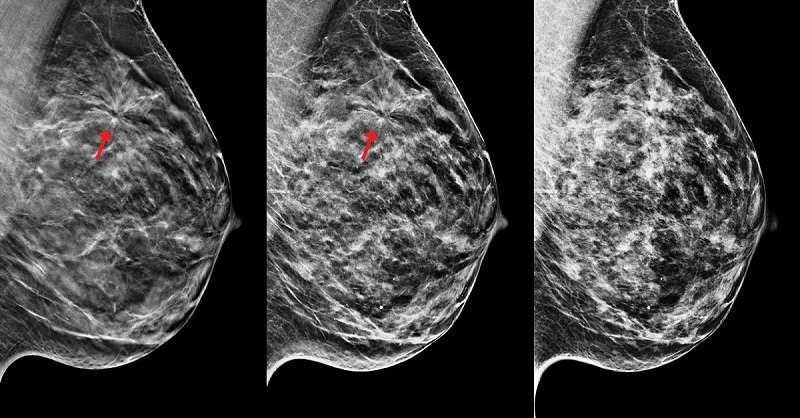

Algunas de estas mujeres fueron sometidos a la terapia con una combinación de fármacos, y algunas sólo a uno de los medicamentos. Para evaluar mejor los resultados del estudio, se tomaron muestras de tejido infectado de la biopsia inicial. Mediante la técnica FISH o hibridación in situ fluorescente se puede determinar el número de copias que posee la paciente, a partir de una biopsia de tejido.

Bueno, no debemos olvidar que la prevención es la mejor medicina. Los exámenes oportunos de mamografía y ginecología, y el autoexamen de mama, contribuyen a un estilo de vida saludable, y son la clave para la salud de la mujer.